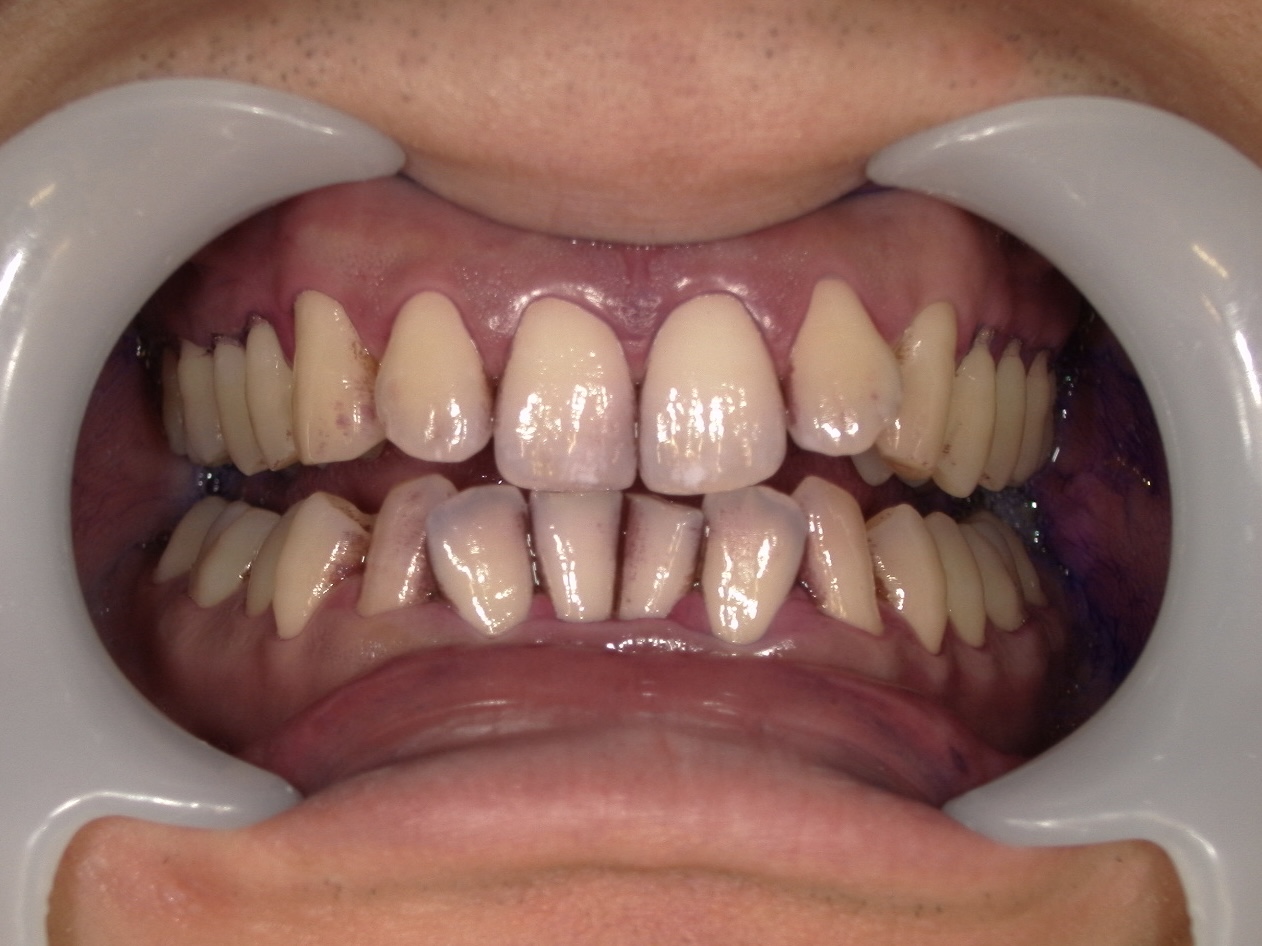

今回ご紹介するのは、定期的な歯みがきはされているものの、下顎前歯の内側(舌側)に強い着色と歯石の付着がついている方のクリーニング前後のお写真をお見せしてどれだけ綺麗になったか比較していこうと思います。

◆クリーニング前の状態(染め出し後)

当院ではクリーニングを行う前に、染め出しを行います。歯垢を染めることによって、「こんな場所にこんなにみがき残しがありますよ」と可視化することで患者様により分かりやすく見ていただくことができます。